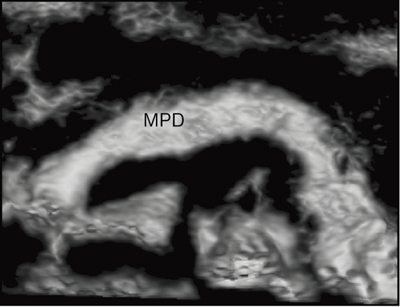

Cavity(USCP)では,主膵管拡張の状態を表現することができる。しかしながら,当然,内腔面の変化はわからない(図7)。膵頭部から膵尾部方向にFly Thruすると,内腔に突出した複数の乳頭状腫瘤を認識できた(図8)。

図7 症例3:IPMNの主膵管(MPD)のCavity(USCP)画像